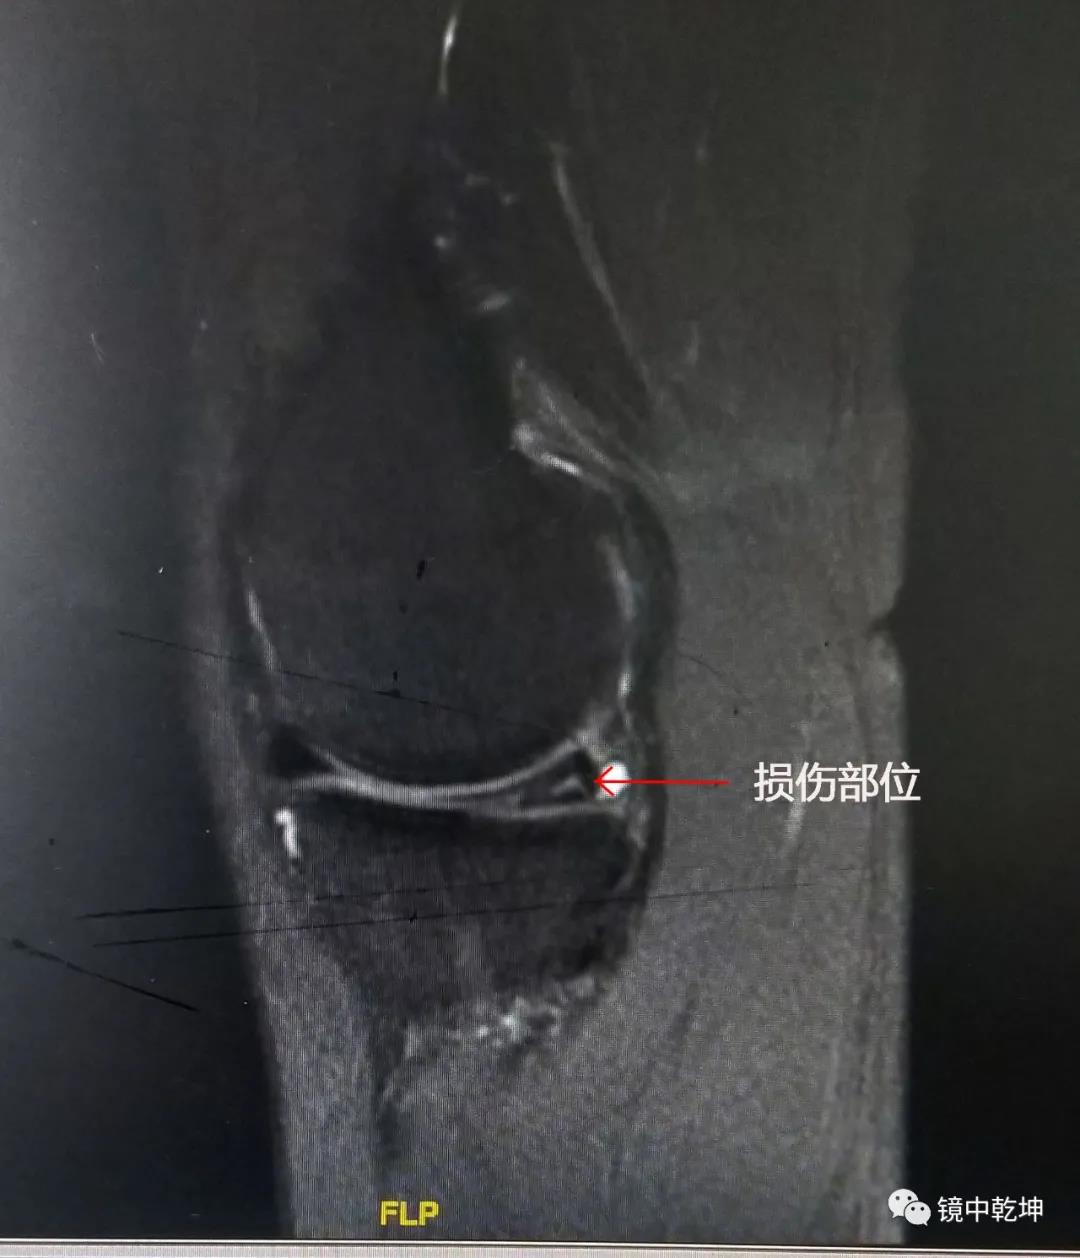

患者陈女士的MRI检查:

南昌大学第二附属医院骨科专家郝亮博士,李晨博士结合陈女士病情,诊断为半月板撕裂伤,并制定了手术方案。